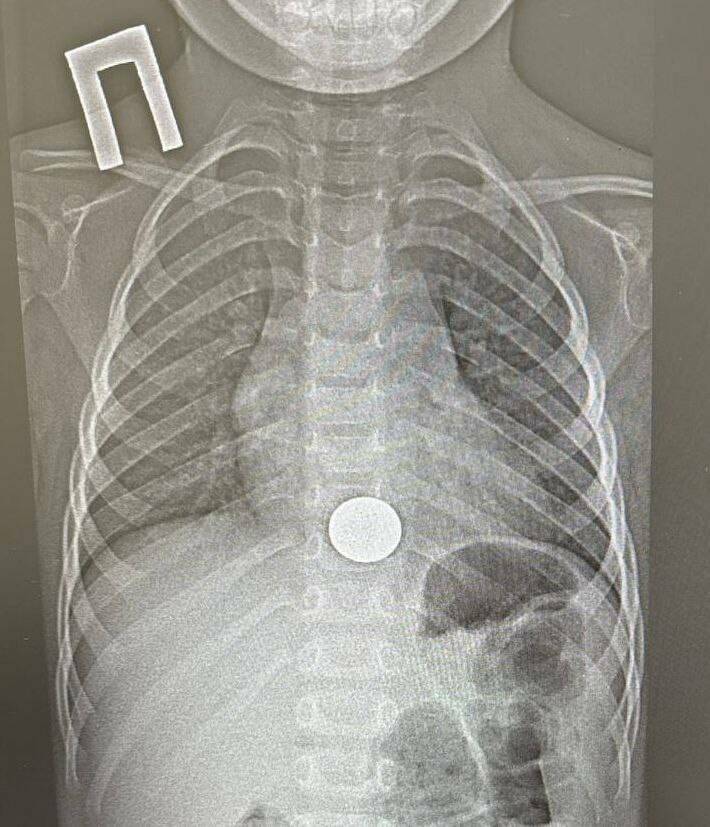

Фото: НДРБ с ПЦ

В Нижнекамске врачи детской районной больницы извлекли монету из пищевода ребенка. Информация появилась в телеграм-канале медицинского учреждения.

Инцидент произошел накануне, 15 декабря. В медучреждение поступил трехлетний ребенок с жалобами на боли за грудиной. Как выяснилось, мальчик случайно проглотил монету. О случившемся он сразу рассказал родителям.

Ребенка оперативно доставили в НДРБ с ПЦ. Детский хирург, врач-эндоскопист Игорь Шогоров удалил инородное тело с помощью эндоскопа. Манипуляция заняла около минуты. После процедуры ребенка для наблюдения перевели в хирургическое отделение, а уже на следующий день, убедившись в его удовлетворительном состоянии, выписали.

Медики отмечают, что своевременное обращение семьи за помощью предотвратило возможные серьезные последствия. При более длительном нахождении монеты в пищеводе она могла травмировать его стенки и привести к опасным осложнениям.